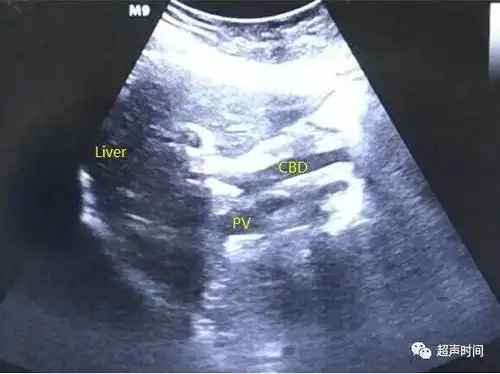

和图 声像图示胆总管(cbd)轻度扩张

门静脉轻度扩张.